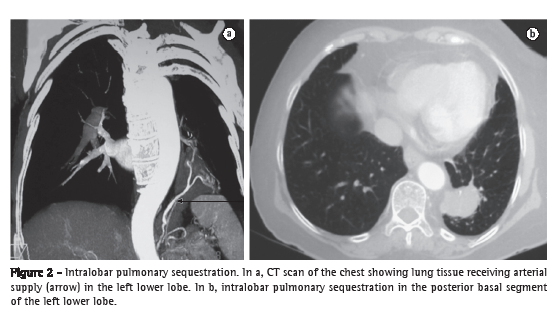

Extralobar pulmonary sequestrations are generally located in the lower lobes of the left lung (80%),(4,13,15,19) in close proximity to the costophrenic sulcus (Figure 1), and are less common than are intralobar pulmonary sequestrations, which account for approximately 75% of all cases of pulmonary sequestrations.(9-11,13,15,18,20) Approximately 10% of all extralobar pulmonary sequestrations are located below the diaphragm.(18) In intralobar pulmonary sequestrations, there is no lung segment predominance(10); however, some authors have reported a greater frequency of intralobar pulmonary sequestrations in the posterior basal segment of the left lower lobe.(5,20) Such sequestrations can go undetected throughout the lifetime of the individual(18) or can manifest as recurrent lower lobe infections.(18)

Both types of pulmonary sequestration receive their blood supply from the systemic circulation (Figure 2), generally via the descending thoracic aorta or the abdominal aorta.(4,11-13,18,19) In approximately 15% of cases, blood supply is provided by a different systemic artery.(11,13,18,19) In intralobar pulmonary sequestration, venous drainage is into the pulmonary veins,(18) whereas it is into the systemic venous system (azygos vein or portal vein) in extralobar pulmonary sequestration.(10,18,19)

In the prenatal period, it can be difficult to diagnose pulmonary sequestration by ultrasound, because extralobar sequestration can be mistaken for a normal lung (the tissues having similar characteristics), whereas intralobar sequestration can be incorrectly diagnosed as congenital cystic adenomatoid malformation (CCAM).(5) Nuclear magnetic resonance imaging can be useful in clarifying the diagnosis in such cases.(22) Extralobar pulmonary sequestration accounts for approximately 23% of the pulmonary lesions that are diagnosed in the prenatal period.(18) Of those, up to 68% can disappear over the course of the prenatal radiological follow-up period.(11) A CT scan of the chest reveals the sequestered lung tissue and its vascularization, as well as other associated malformations, if present.(11,15) The test of choice for the postnatal diagnosis is CT angiography.(11,13,15,18) Until recently, conventional angiography was the gold standard for demonstrating the arterial supply and venous drainage of such lesions. Currently, CT angiography is used instead of conventional radiography because the former is less invasive and more efficient in diagnosing such lesions, showing the vascularization of the sequestered tissue in great detail and therefore allowing safer surgical planning.(10-12,19,23)